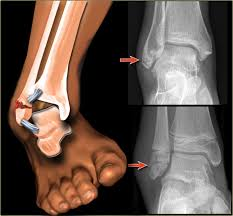

ankle sprain on xray looks like

ankle rolled outward and foot turns inward